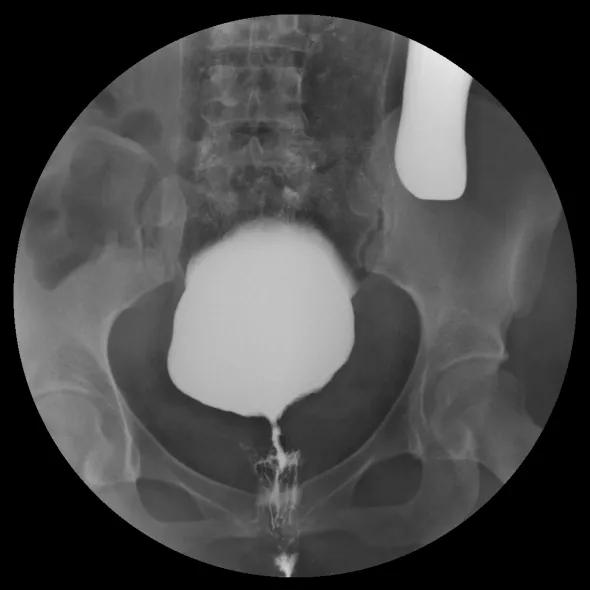

△直肠远端前壁→阴道内可见造影剂显示

小静不仅 直肠阴道瘘复发